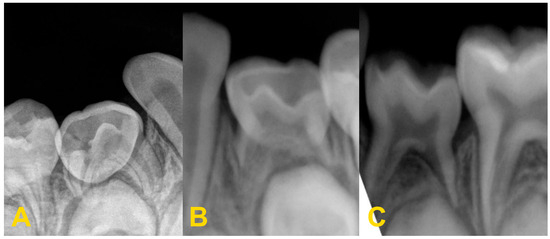

Figure 8.

Severe reinclusion of tooth no. 75 causing infraposition of the tooth no. 36: (A) panoramic X-ray, (B) preoperative intraoral photography—teeth nos. 75 and 36 are missing in the oral cavity, (C) intraoral photography—after elevation of the mucoperiosteal flap, (D) intraoral photography—osteotomy, (E) intraoral photography—crown–root separation, (F) fragments of extracted tooth no. 75, (G) intraoral photography—osteotomy and exposure of tooth no. 36, (H) intraoral photography—stitching the wound, and (I) intraoral photography—healing on the 7th day after the procedure.

In the case of severe infraocclusion, the treatment of choice is tooth extraction. The procedure can be very complicated due to the tilt of the teeth relative to the gap and the difficult access, as well as root dilaceration. The adjacent teeth could be uprighted with an orthodontic appliance to make the surgical procedure easier. Often, the procedure requires coronal–root separation of the tooth, mucoperiosteal flap elevation, and osteotomy [37,38,39,40]. In the case of reincluded teeth into the maxillary sinus, it may open, and cause complications related to the maxillary sinus, such as the oro–sinus communication, oro–sinus fistula, or maxillary sinusitis. The roots of submerged teeth in the mandible may be located deep in the body of the mandible and surrounding or entwining the inferior alveolar nerve canal or the lower border of the mandible. If it is necessary to remove a tooth, it may result in disruption of the neurovascular bundle, bleeding, damage to the inferior alveolar nerve, or sensory disturbances. If there is significant bone loss during the extraction of such a tooth, the area may require miniplate osteosynthesis. This is a place of reduced resistance and may result in a fracture of the mandible [37,38,39,40,41,42,43].